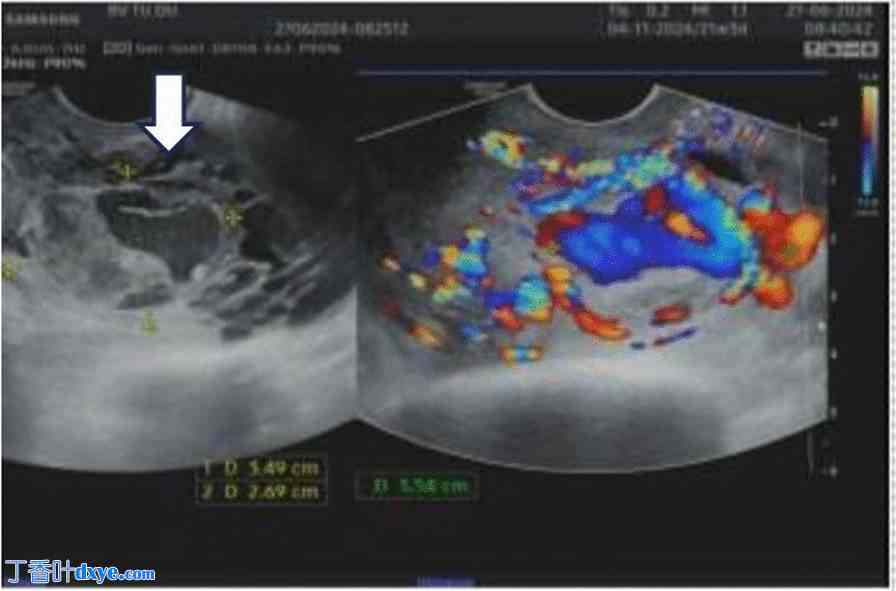

图 4.

灰阶超声图像(黑白)显示子宫肌层内存在不规则、不均匀、低回声、弯曲的结构(白色箭头)(A)。扩张的血管呈螺旋状,类似于静脉曲张并伴有瘘管。观察到弯曲的扩张血管网络,并伴有湍流(B)。